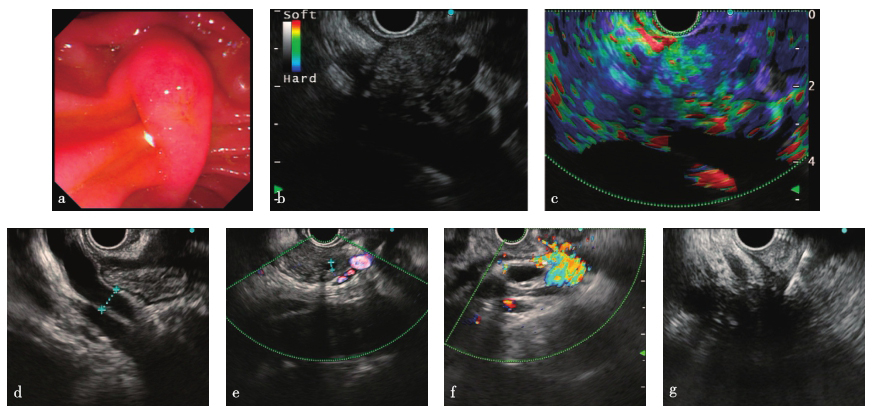

内镜下见十二指肠乳头未见异常;胰腺头部见一低回声病变,边界欠清,横截面大小约3.09cm×2.72cm,多普勒显示少许血流信号,弹性成像为3分;胰腺体部主胰管直径3.0mm;体部及尾部胰腺萎缩;胆总管下段管壁增厚明显,腹腔内可见多发肿大淋巴结(图2)。EUS-FNA病理学检查:胰腺多量血凝块内见少量小肠黏膜;胰腺穿刺涂片,多量红细胞内见极少数异性细胞;十二指肠乳头,小肠组织示慢性炎。免疫组化:十二指肠内淋巴细胞表达IgG(+),IgG4∶IgG<40%,IgG4<50个/HP(图3)。

图2 EUS-FNA检查

a. 十二指肠乳头;b. 胰腺头部占位;c. 胰腺头部占位弹性成像;d. 主胰管;e. 胆总管;f. 腹腔多发淋巴结;g. FNA穿刺